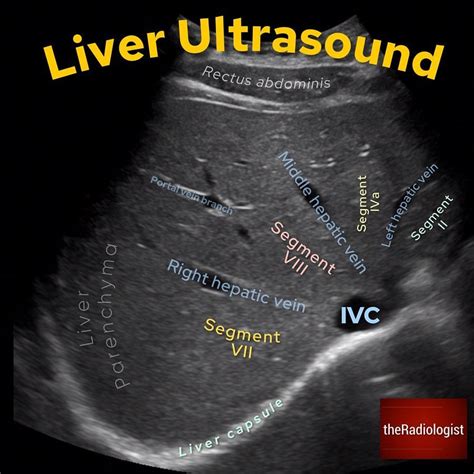

Secondly, the echogenicity or texture of the liver tissue is assessed. This refers to how the liver tissue reflects the sound waves. On an ultrasound, the liver appears as a gray, speckled pattern. A normal liver has a homogeneous, or uniform, echotexture. This means that the sound waves are reflected consistently throughout the liver. The liver tissue should be slightly more echogenic (brighter) than the kidney cortex (the outer part of the kidney). The blood vessels within the liver, like the portal veins and hepatic veins, appear as dark, anechoic (echo-free) structures. Any significant changes in echogenicity could indicate a problem, such as fatty liver disease (where the liver appears brighter) or cirrhosis (where the liver texture becomes more uneven).

Thirdly, the blood vessels within the liver are evaluated. The radiologist will look at the portal vein, which carries blood from the digestive system to the liver, and the hepatic veins, which drain blood from the liver back to the heart. The vessels should be clearly visible and have a normal appearance. Any blockages or abnormalities in these vessels can point to underlying issues like portal hypertension (high blood pressure in the portal vein) or blood clots.